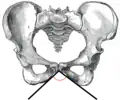

![]() Female pelvis (pubic arch labeled at bottom center) | |

Female subpubic angle